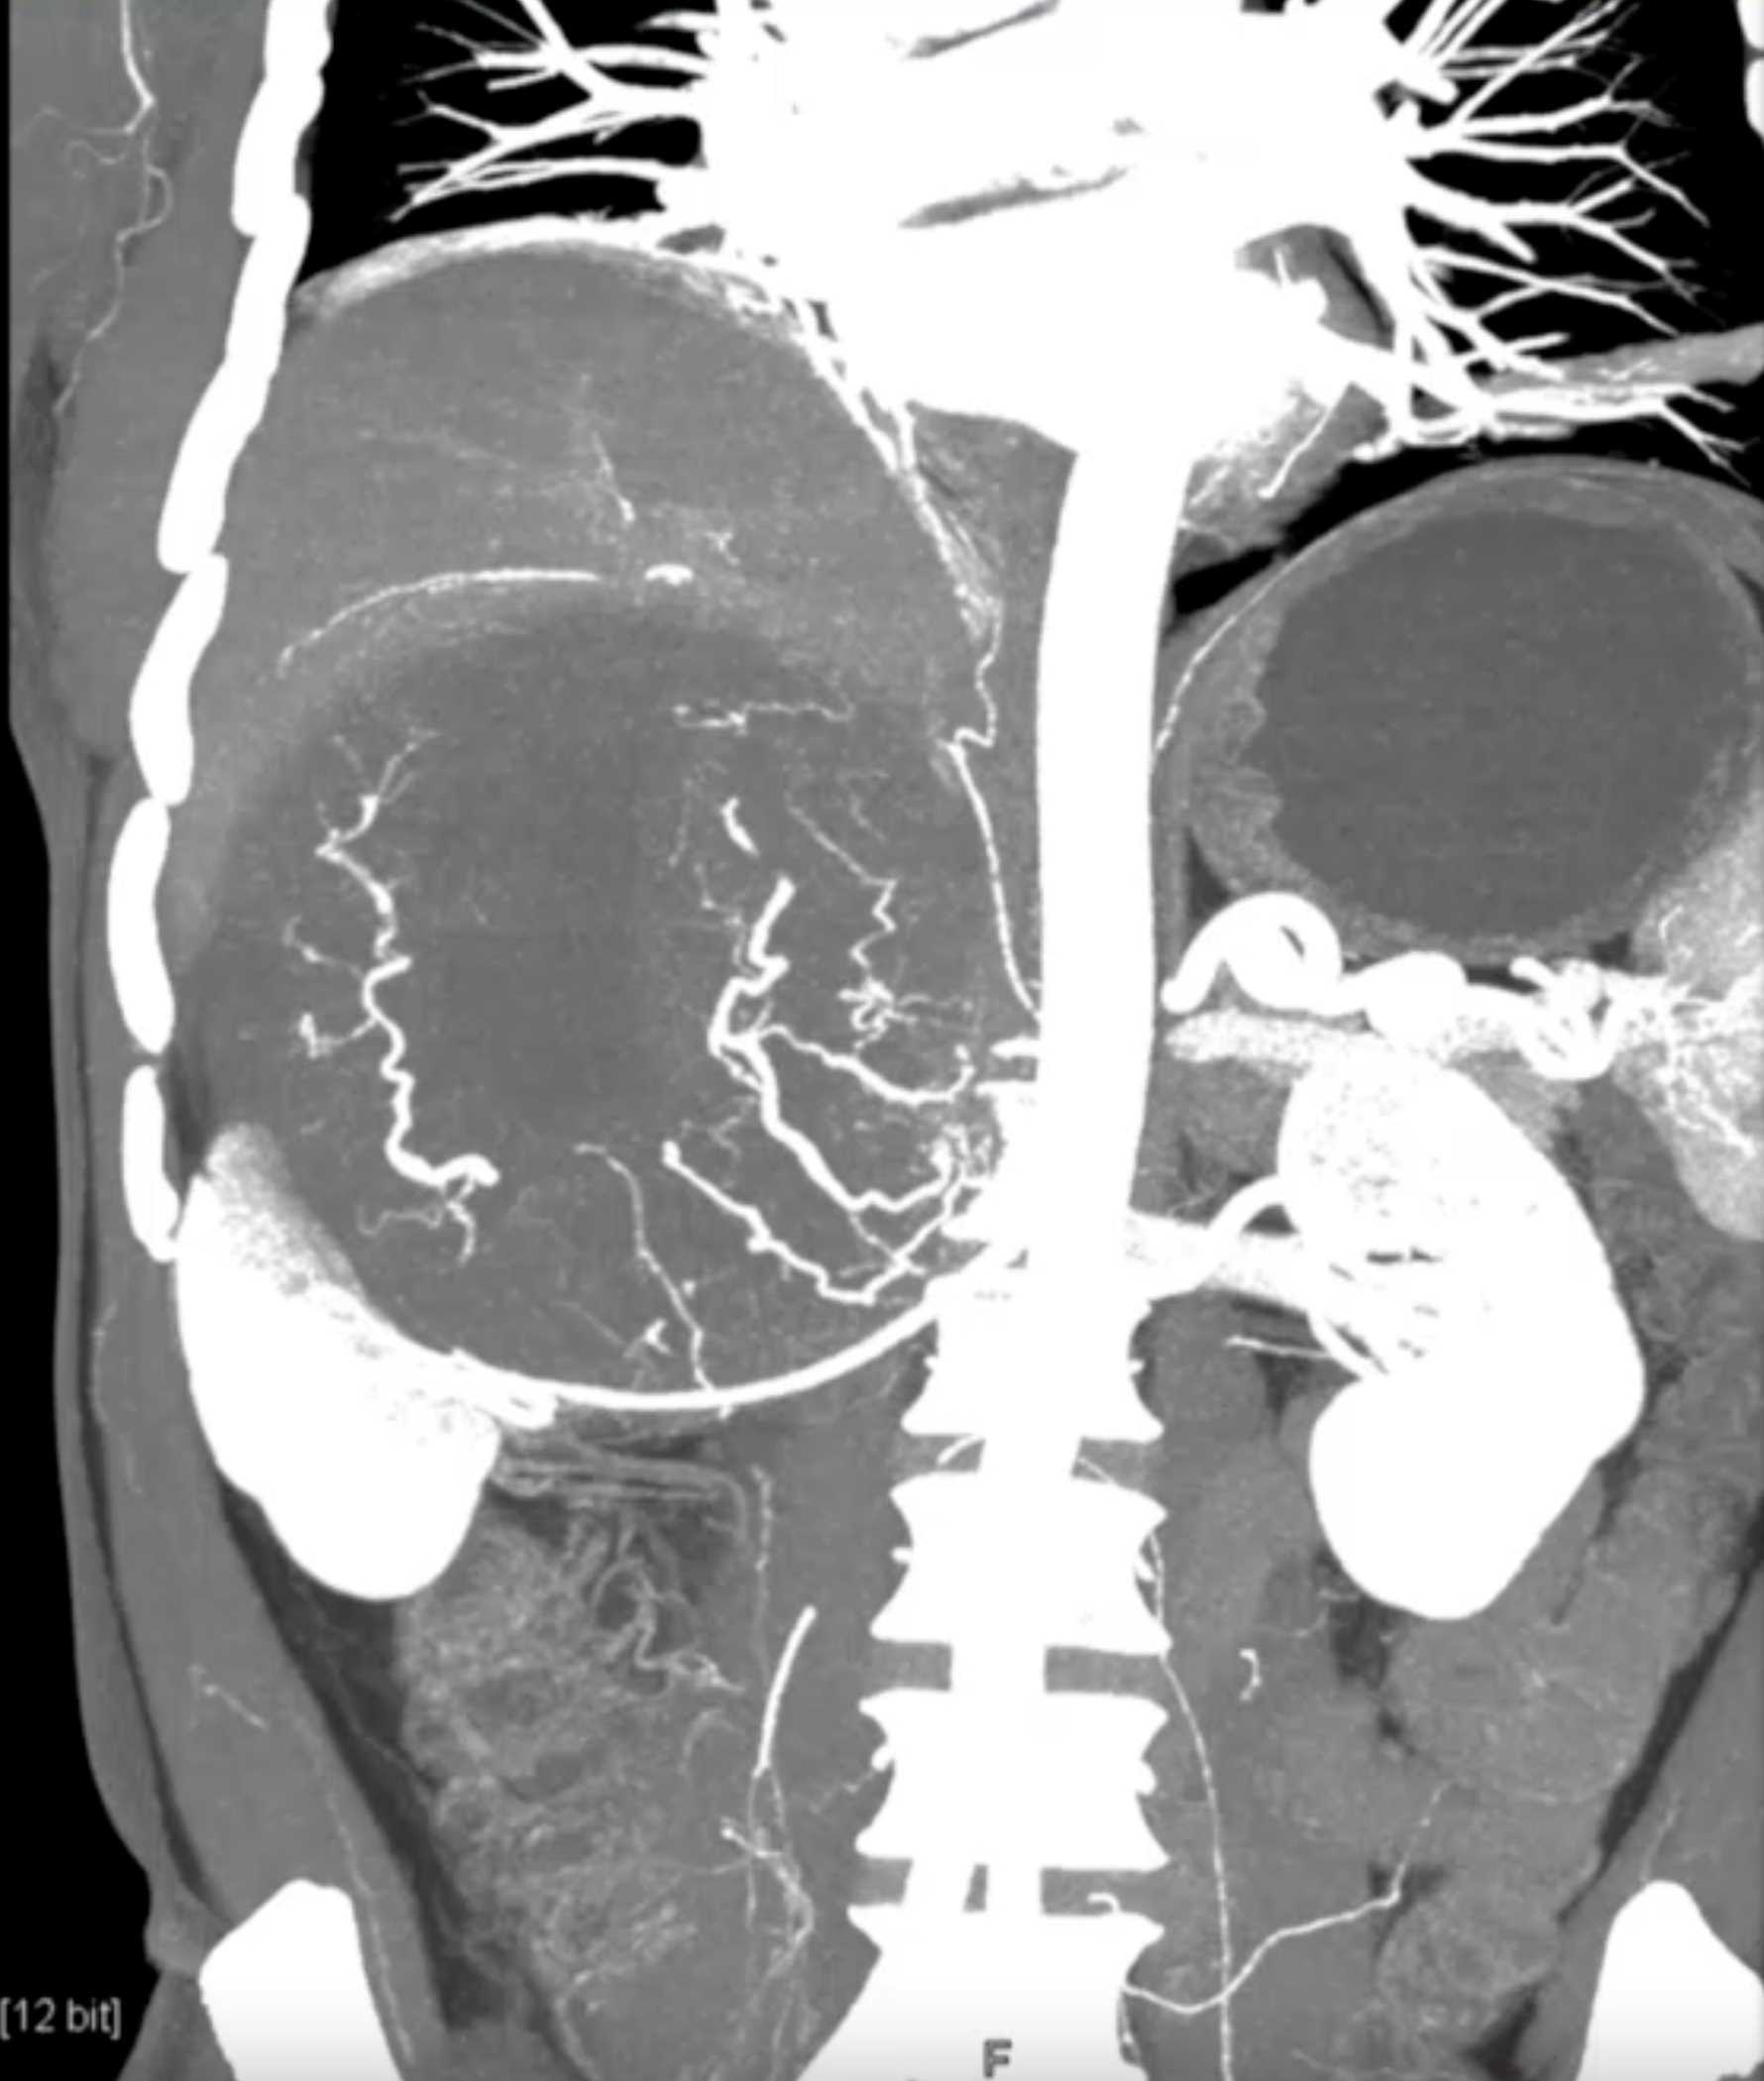

Left Adrenal Metastases from Renal Cell Carcinoma